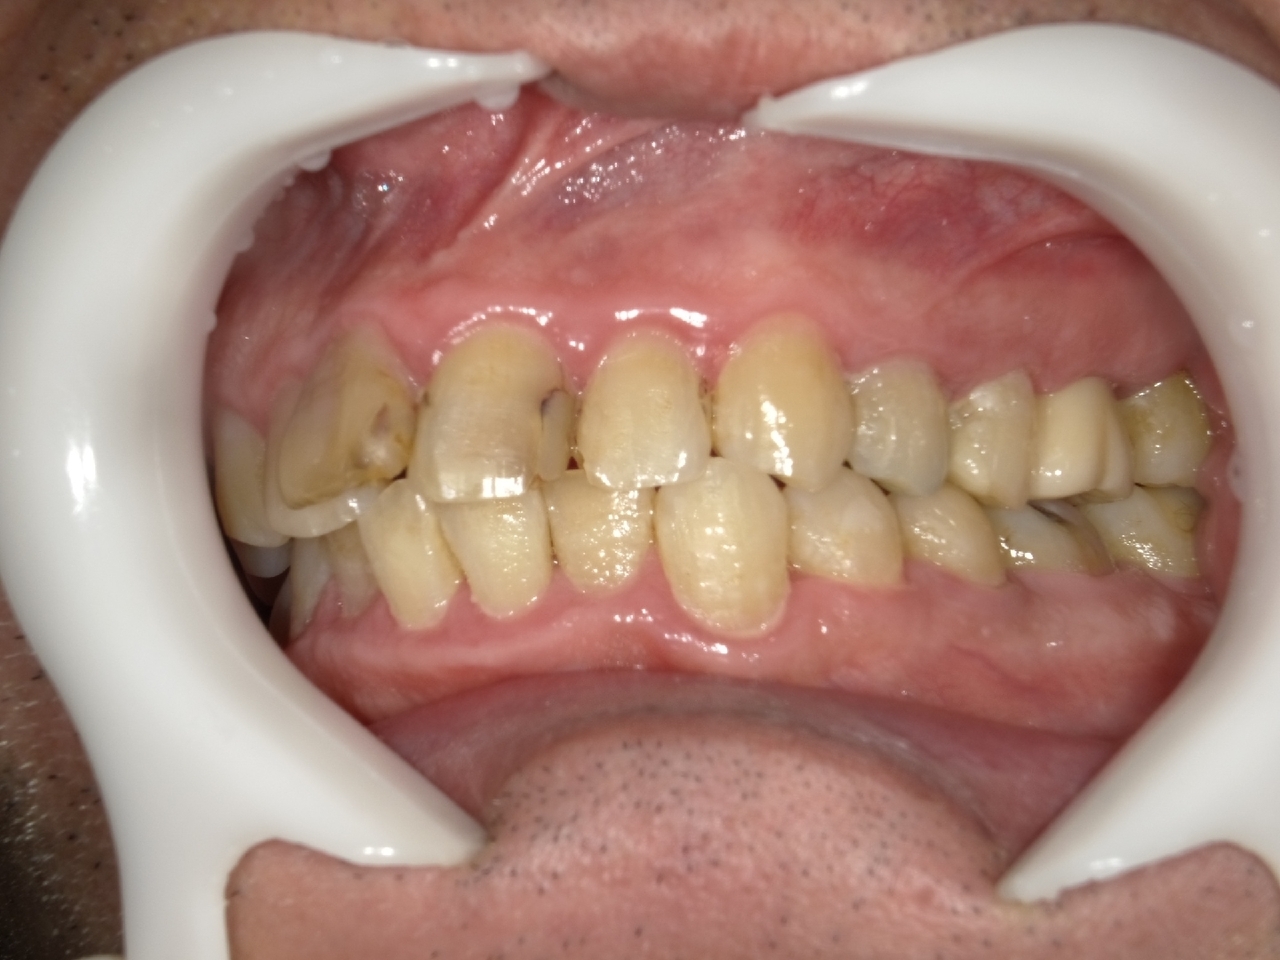

5.左上4番のインプラント抜歯即時埋入、左上6番の上顎既存骨1から2mmのグラフトレスサイナスリフト、左下56の大幅な骨欠損により、下顎神経の損傷を回避するために、ショートインプラントを使用し、左下56にインプラントを埋入し、最終補綴物は、左上456の3ユニットのジルコニアブリッジし、左下56は、ジルコニアの連結冠を装着したケース

After

枚方市のインプラントの症例

M・I 様 女性 70代

症状としては、左下56は、歯周病で欠損したと考えられるが、かなりの骨欠損をともなっていた。左上456に関しては、動揺が大きく、炎症が起き、排膿、および、歯性上顎洞炎を起こしていた。

治療法としては、動揺がひどくなってきて、炎症の症状もあったため、左上56の抜歯を希望。インプラント治療をその後、希望したため、左上4に関しては抜歯即時埋入。左上6に関しては、既存骨1から2mmでインプラント治療が厳しい状態であったが、グラフトレスサイナスリフトを行い、治療期間5か月はかかるということを説明して、インプラント埋入をおこないました。その後、2か月半後、大幅に骨が欠損している下顎56に対して、ショートインプラントを使用して、下顎神経の損傷を避けて、インプラント埋入を終えています。その後2か月後に光学印象で印象を行い、上顎刺億456歯、3ユニットのジルコニアブリッジを装着。下顎左側56に関しては、骨欠損が大きいため、歯冠長がだいぶ長くなるため、ジルコニアの連結冠を装着して治療を終えた。

治療結果は、上顎6に関しては、既存骨が少なく、厳しい治療ではありましたが、5か月で治療を終え、患者様の負担を最小限に抑えるができたと考えます。(従来のサイナスリフトでは、このようなケースでは1年以上、1年程度の治療期間がかかるか、治療が不可能と言われるケースだと考えます。)また、下顎は骨欠損が大きく、下歯槽管のリスクが起きることが考えられますが、ショートインプラントを使用することで安全に治療を行うことができました。

治療の期間・回数:治療期間5か月(上顎456 3ピースブリッジの治療は5か月(上顎既存骨が2mm程度しかなく、骨結合に時間がかかるケースであったために、5か月の治療期間が必要であった。)(左下56に関しては2か月半で治療を終えています。)治療回数は、13回。

治療の価格:1,474,000円(税込)

治療費の内訳:左上46および左下56のインプラント基本料(フィックスチャー及び手術費用、投薬費用、レントゲン費用、インプラント上部費用(アバットメントおよびジルコニアクラウンの費用用)330000円(税込み)×4本分 1320000円(税込)。左上5ジルコニアポンテック費用88000円(税込)。オプション費用、左上4抜歯即時埋入加算(人工骨費用を含む)+グラフトレスサイナスリフト費用 33000円(税込)、左上6グラフトレスサイナスリフト費用 33000円(税込)

治療のリスクや副作用:手術後に、痛みや腫れ、出血、合併症などを引き起こす可能性があります。噛む感覚がご自身の歯と異なる場合があります。見た目がご自身の歯と異なる場合があります。手術後にメインテナンスを継続しないと、インプラントが抜け落ちる可能性があります。